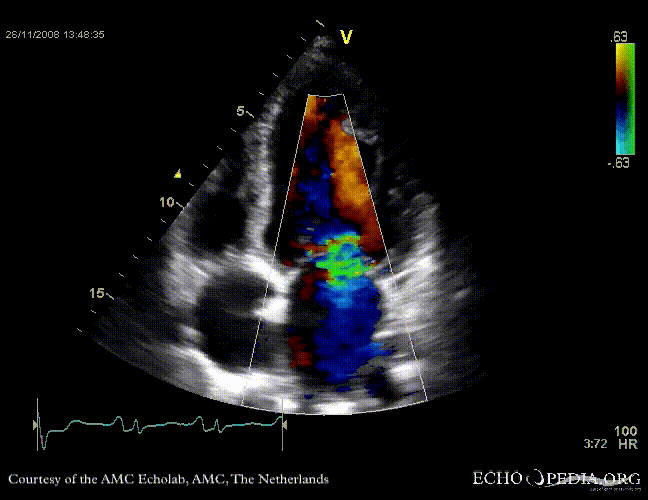

Dilated cardiomyopathy with severe mitral valve regurgitation

Courtesy of: J. Vleugels, AMC, The Netherlands